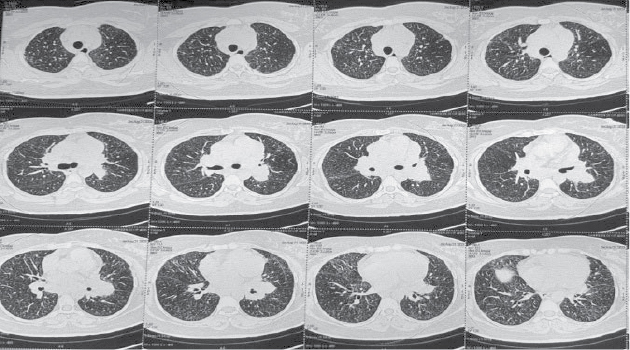

kidneys with mildly increased bilateral cortical echogenicity. Contrast-enhanced computed tomography (CECT) thorax was not feasible as creatinine was high, so noncontrast computed tomography (NCCT) thorax was done which showed multiple enlarged

mediastinal and hilar lymph nodes with minimal thickening of interlobular and intralobular septae in both lungs with areas of ground-glass opacities and diffuse centrilobular nodules(Figs. 1 and 2). Inter stitial lung disease work up sent,

Figure

1. NCCT Thorax - Centrilobular nodules and septal thickening in parenchymal window.